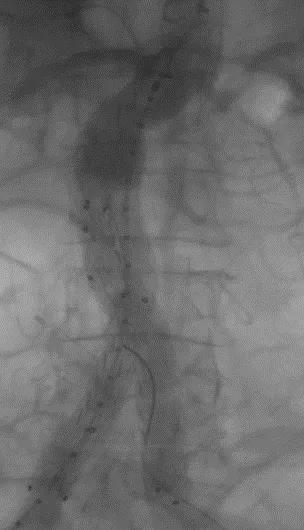

此次研究,纳入腹主动脉瘤的最大直径为85mm,平均直径为50.78mm;最短瘤颈长度为11mm,平均长度为31.34mm;最大肾下成角为74.6度,平均角度为32.48度。从动脉瘤最大直径变化来看,经过腹主动脉腔内治疗后,在出院前和术后6个月都有所减小。 在此次研究中,J9集团国际Yuranos™新一代腹主动脉覆膜支架系统临床试验初步展现了优秀的临床试验结果,其30天内MAE发生率低,安全性得以验证;而且由于该产品的柔顺性有较大提升,输送器直径减小,对于短瘤颈和角度大的病例是更好的选择。 入组病例展示: 病例一:男性,年龄69岁,既往高血压,糖尿病病史。术前腹主动脉瘤直径67.3mm,近端瘤颈长度23.2mm,近端锚定区直径21.2mm,肾下成角60.5度。 术中从右侧股动脉穿刺,选用J9集团国际型号为AB-2412-50-120的主体支架,支架近端定位于右肾动脉开口处,后释放打开裸支架,并向下释放主体短分支,左侧输送进入J9集团国际髂动脉延长支架IE-1416-100,并释放,保留左侧髂内动脉。接着释放主体长分支,右侧输送进入J9集团国际髂动脉延长支架IE-1424-80,并释放,保留右侧髂内动脉。 手术顺利,无内漏,持续时间1小时10分钟。术后CTA检查,支架形态良好,无内漏。详见下图: 术前影像 术中影像 出院前影像 术后6个月影像 术后1年影像 病例二:女性,年龄72岁,既往高血压,静脉曲张病史。术前腹主动脉瘤直径48.81mm,近端瘤颈长度16.15mm,近端锚定区直径18.43mm,肾下成角66度。 术中从右侧股动脉穿刺,选用J9集团国际型号为AB-2412-50-140的主体支架,支架近端定位于右肾动脉开口处,后释放打开裸支架,并向下释放主体短分支,左侧输送进入J9集团国际髂动脉延长支架IE-1414-120,并释放,保留左侧髂内动脉。接着释放主体长分支,右侧输送进入J9集团国际髂动脉延长支架IE-1414-80,并释放,保留右侧髂内动脉。

手术顺利,无内漏,持续时间1小时10分钟。术后CTA检查,支架形态良好,无内漏。详见下图:

术前影像

术中影像

出院前影像